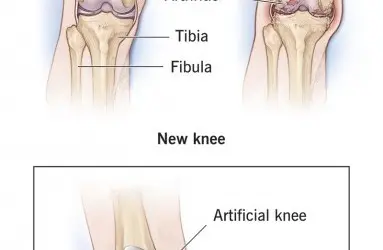

- Diz Protezi

- Total Eklem Protezi (Kalça, diz, diğer)

ROSA (Robotik Cerrahi Asistan), diz ve kalça protezlerini tam ölçüsüne göre ayarlayarak, daha hızlı iyileşme ve fonksiyonların düzelmesini sağlayan bir robotik cihazdır.